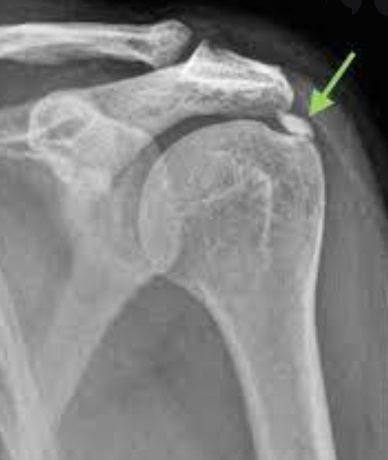

석회성 힘줄염은 말 그대로 어깨 힘줄에 석회(칼슘)가 침착되어 염증을 일으키는 질환이에요. 아직까지 정확한 원인은 밝혀지지 않았지만, 주로 힘줄의 퇴행성 변화나 미세한 손상, 혈류 감소 등이 원인으로 지목되고 있습니다. 30~50대 연령층에서 비교적 흔하게 나타나는데, 특히 어깨를 많이 사용하는 직업이나 반복적인 운동을 하는 분들에게 더 잘 생긴다고 해요. 꼭 나이가 많아야 생기는 건 아니라는 거죠.

석회성 힘줄염의 가장 특징적인 증상은 뭐니 뭐니 해도 극심한 통증이에요. 특히 통증이 갑자기 시작되는 경우가 많고, 통증 때문에 팔을 움직이는 것이 힘들어집니다. 통증의 시기와 강도에 따라 보통 3단계로 나누어 설명하곤 해요.